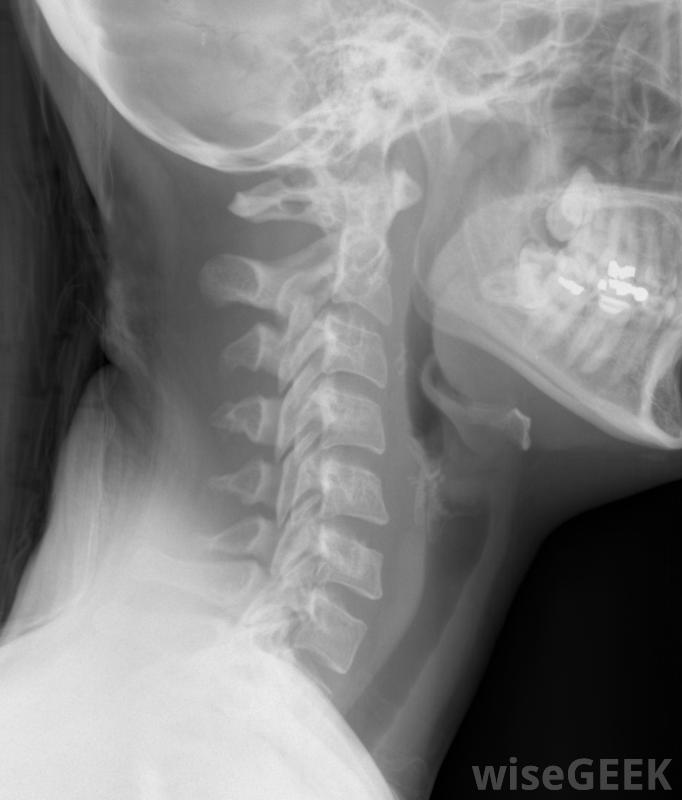

頸椎由七根脊椎組成,支撐著大腦和頭骨。它保護著身體上部的各種神經,如臉、頸、喉、臂和手。頸領,也稱為頸托或頸托,用于支撐頭部和脊髓的頸部。它限制頸部和脊椎的運動,使損傷得以愈合,并有助于防止損傷的發生。頸部X光片,包括頸椎。頸托通常用于緊急情況下和短期治療。當頭部或頸部受傷時,脊髓損傷的危險是一個值得關注的問題。在緊急情況下,頸環通常被放置在適當的位置上,以防止這種情況的發生。頸環有時也用于治療頸部疼痛,如頸部扭傷,并使脊髓重新排列戴頸領的婦女。有四種基本類型的頸領:軟泡沫、凝膠填充的熱敷或冷敷、泡沫固定和胸骨枕下頜骨固定器(SOMI)的一種支架。它可以牢固地固定在頸部和上身,通常用尼龍搭扣或其他簡單的帶子固定。它們有各種尺寸,一般很容易清洗。頸托通常被制作成隨時佩戴,包括在睡覺時事故發生后,有時建議使用頸部項圈來治療嚴重的頸部扭傷。軟泡沫項圈可幫助減輕頸部輕微損傷引起的肌肉緊張或疼痛。這是最常見的一種頸領,也是最經濟的一種。軟泡沫項圈只適合頸部,所以頸部活動范圍有限。對于頸部輕微損傷,如僵硬或炎癥,通常使用凝膠填充的熱敷或冷敷領口。類似于軟泡沫領,這種領子里的包是冷凍或加熱的,放在針織或尼龍袖子里,固定在脖子上。這些類型的領子比一般的加熱墊和冰袋要省事泡沫固定項圈,也稱為費城頸部項圈,通常用于在軟組織損傷后幫助加強頸部,比如頸部扭傷或頸部扭傷。致密的泡沫塑料項圈位于肩膀上部,頸部高度可調,使下巴能夠舒適地休息,大多數都有氣管切開的開口。通常在上身安裝一個索米支架來限制頭部、頸部、關節和脊柱的運動。這種類型的項圈通常用于治療頸椎骨折,脊髓損傷和嚴重的頭頸部創傷它通常是在醫院里穿的,而且通常在任何時候都穿著,即使是在洗澡或穿衣的時候,黑色或棕褐色。藥店或零售店通常出售軟泡沫或凝膠填充的頸環。其他頸環通常需要醫生處方,因為它們是為每個人量身定制的。頸領可用于治療頸部疼痛或重新排列脊髓。